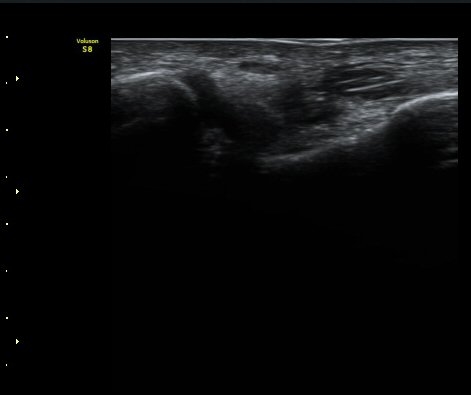

Àüºñ°ñ°æ°ñÀδë Á¾´Ü¸é°Ë»ç¿¡¼­ ƯÀÌ ¼Ò°ßÀ» º¸ÀÌÁö ¾Ê´Â´Ù(±×¸² 2).

±×¸²2) Àüºñ°ñ°æ°ñÀδë Á¾´Ü¸é°Ë»ç±Û